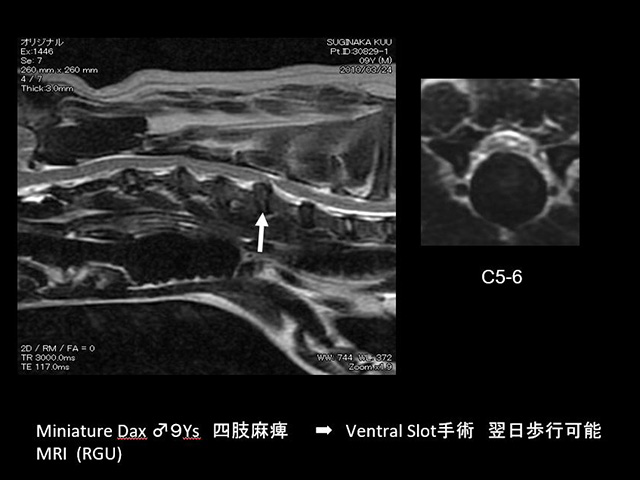

椎間板ヘルニア/その他Intervertebral Disc Hernia

椎間板ヘルニアとは、脊椎椎体間にありショックアブソーバーの役割を担う椎間板が、破裂による椎間板物質の逸脱や、椎間板の突出により脊柱管内の脊髄が圧迫され神経傷害を起こす救急疾患です。